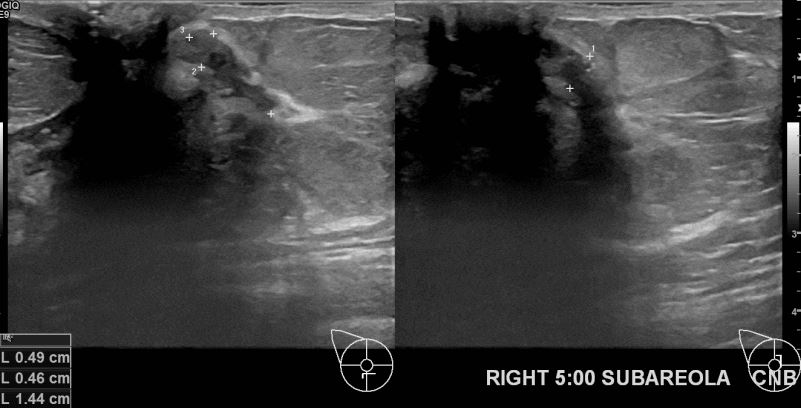

상기환자 건진상 이상소견으로 조지검사권유받고 내원하신 30대 여성분으로 우측유방멍울 조직검사시행후 유방암 진단되었습니다